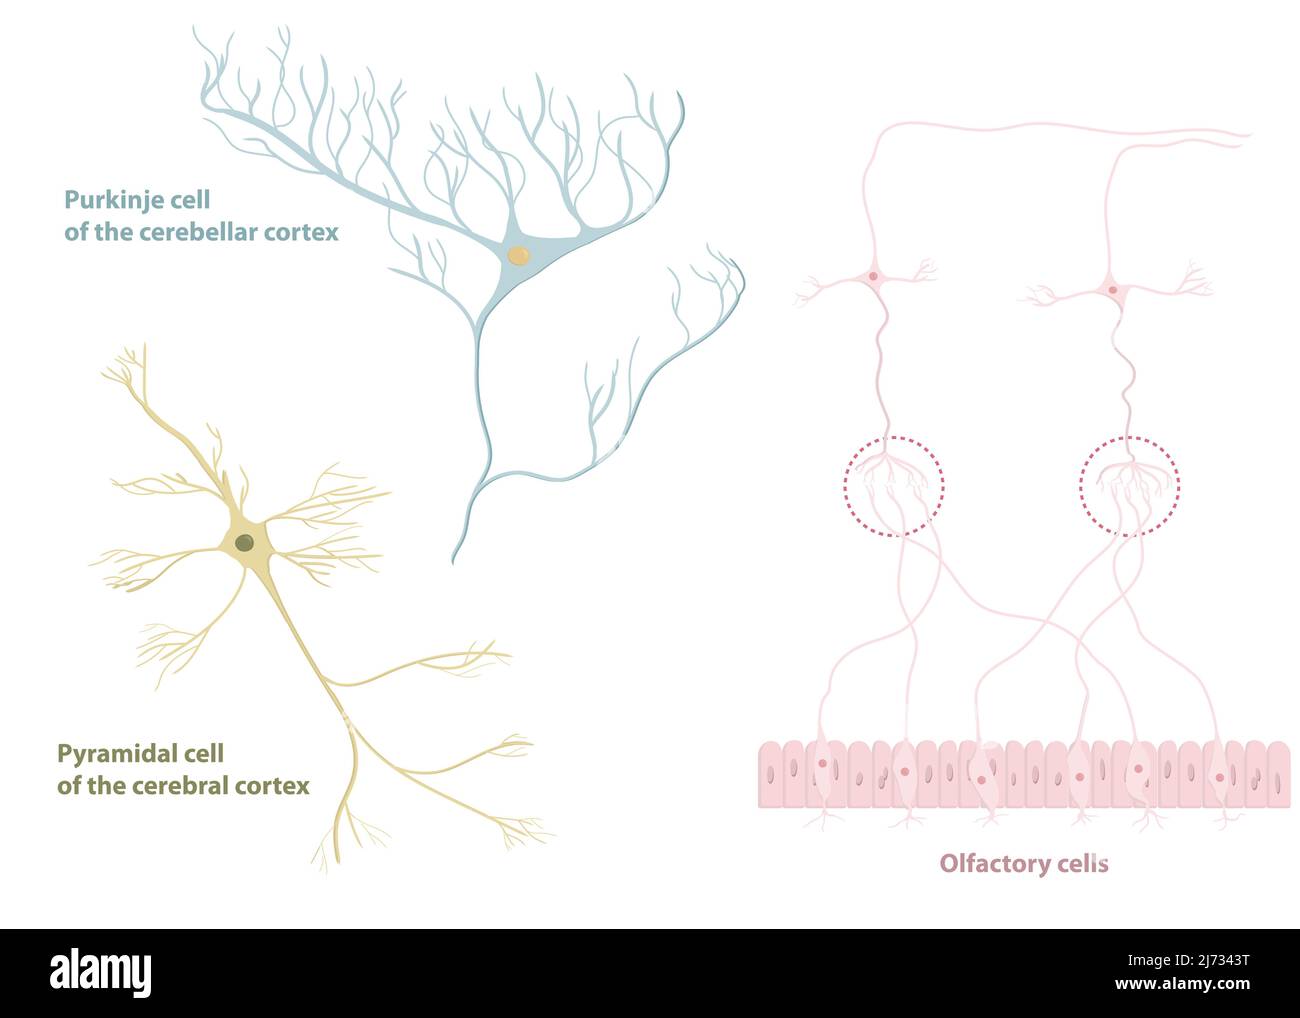

RF2J7343T–Tipi di neuroni: Cellule piramidali della corteccia cerebrale, cellule Purkinje della corteccia cerebrale, cellule olfattive dell'epitelio olfattivo